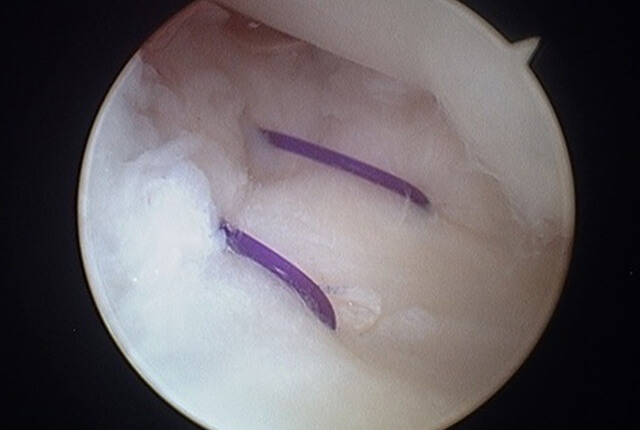

まずは手関節鏡視下にTFCCを観察します。

TFCC損傷の状況、尺骨variance、DRUJ不安定性などから手術方法を決定します。

TFCC縫合術

DRUJ不安定性高度のTFCC損傷は尺骨遠位に縫合する手術法があります。

TFCC再建術

陳旧例では他部位の腱を利用する手術法がありす。